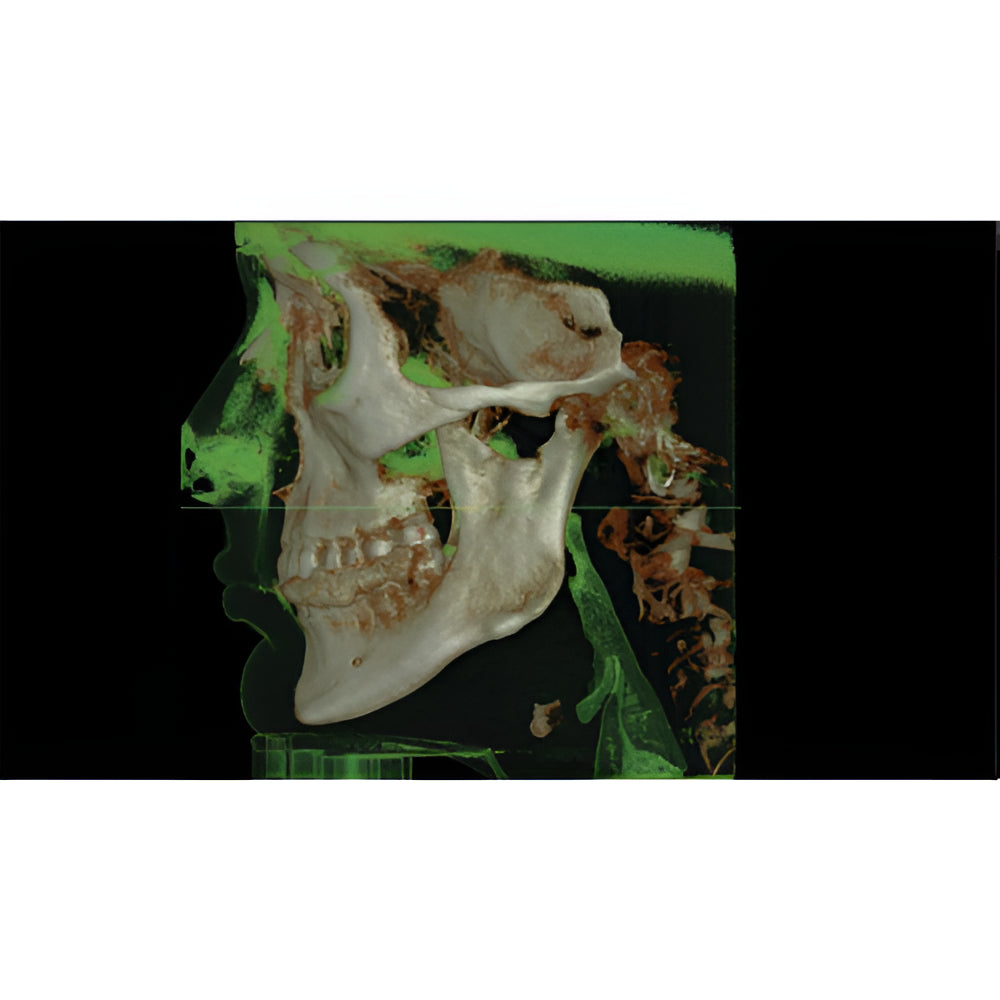

The Vatech PaX-i3D Green panoramic plus cone beam system delivers large field of view (up to 15 x 15 cm) dental CBCT scans in addition to standard 2D panorex and extraoral bitewing X-ray images. This Vatech CBCT machine features the innovative green CT technology which minimizes patient dose, while the Rapid Scan feature delivers high-quality 3D cone beam scans in just 5.9 seconds. A quick exposure time helps to minimize artifacts and motion, while at the same time reducing patient dose, making your imaging process more efficient and safer.

- 3D Cone Beam

- Large FOV

- Multi-FOV

- Focused FOV